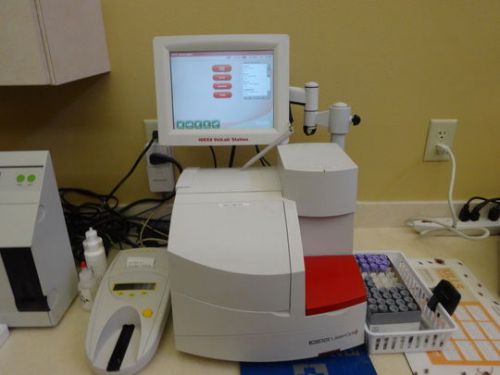

IDEXX Vettest 8008, electrolyte, QBC and centrifuge

Idexx In House Veterinary lab equipment